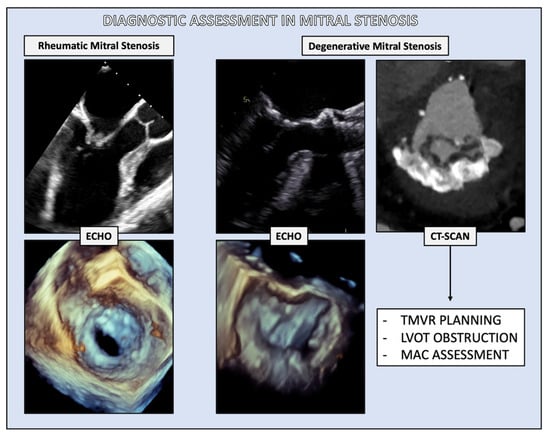

2. Diagnosis

2.1. Morphological Features

2.2. Mitral Valve Area (MVA)

2.5. Evaluation of MAC